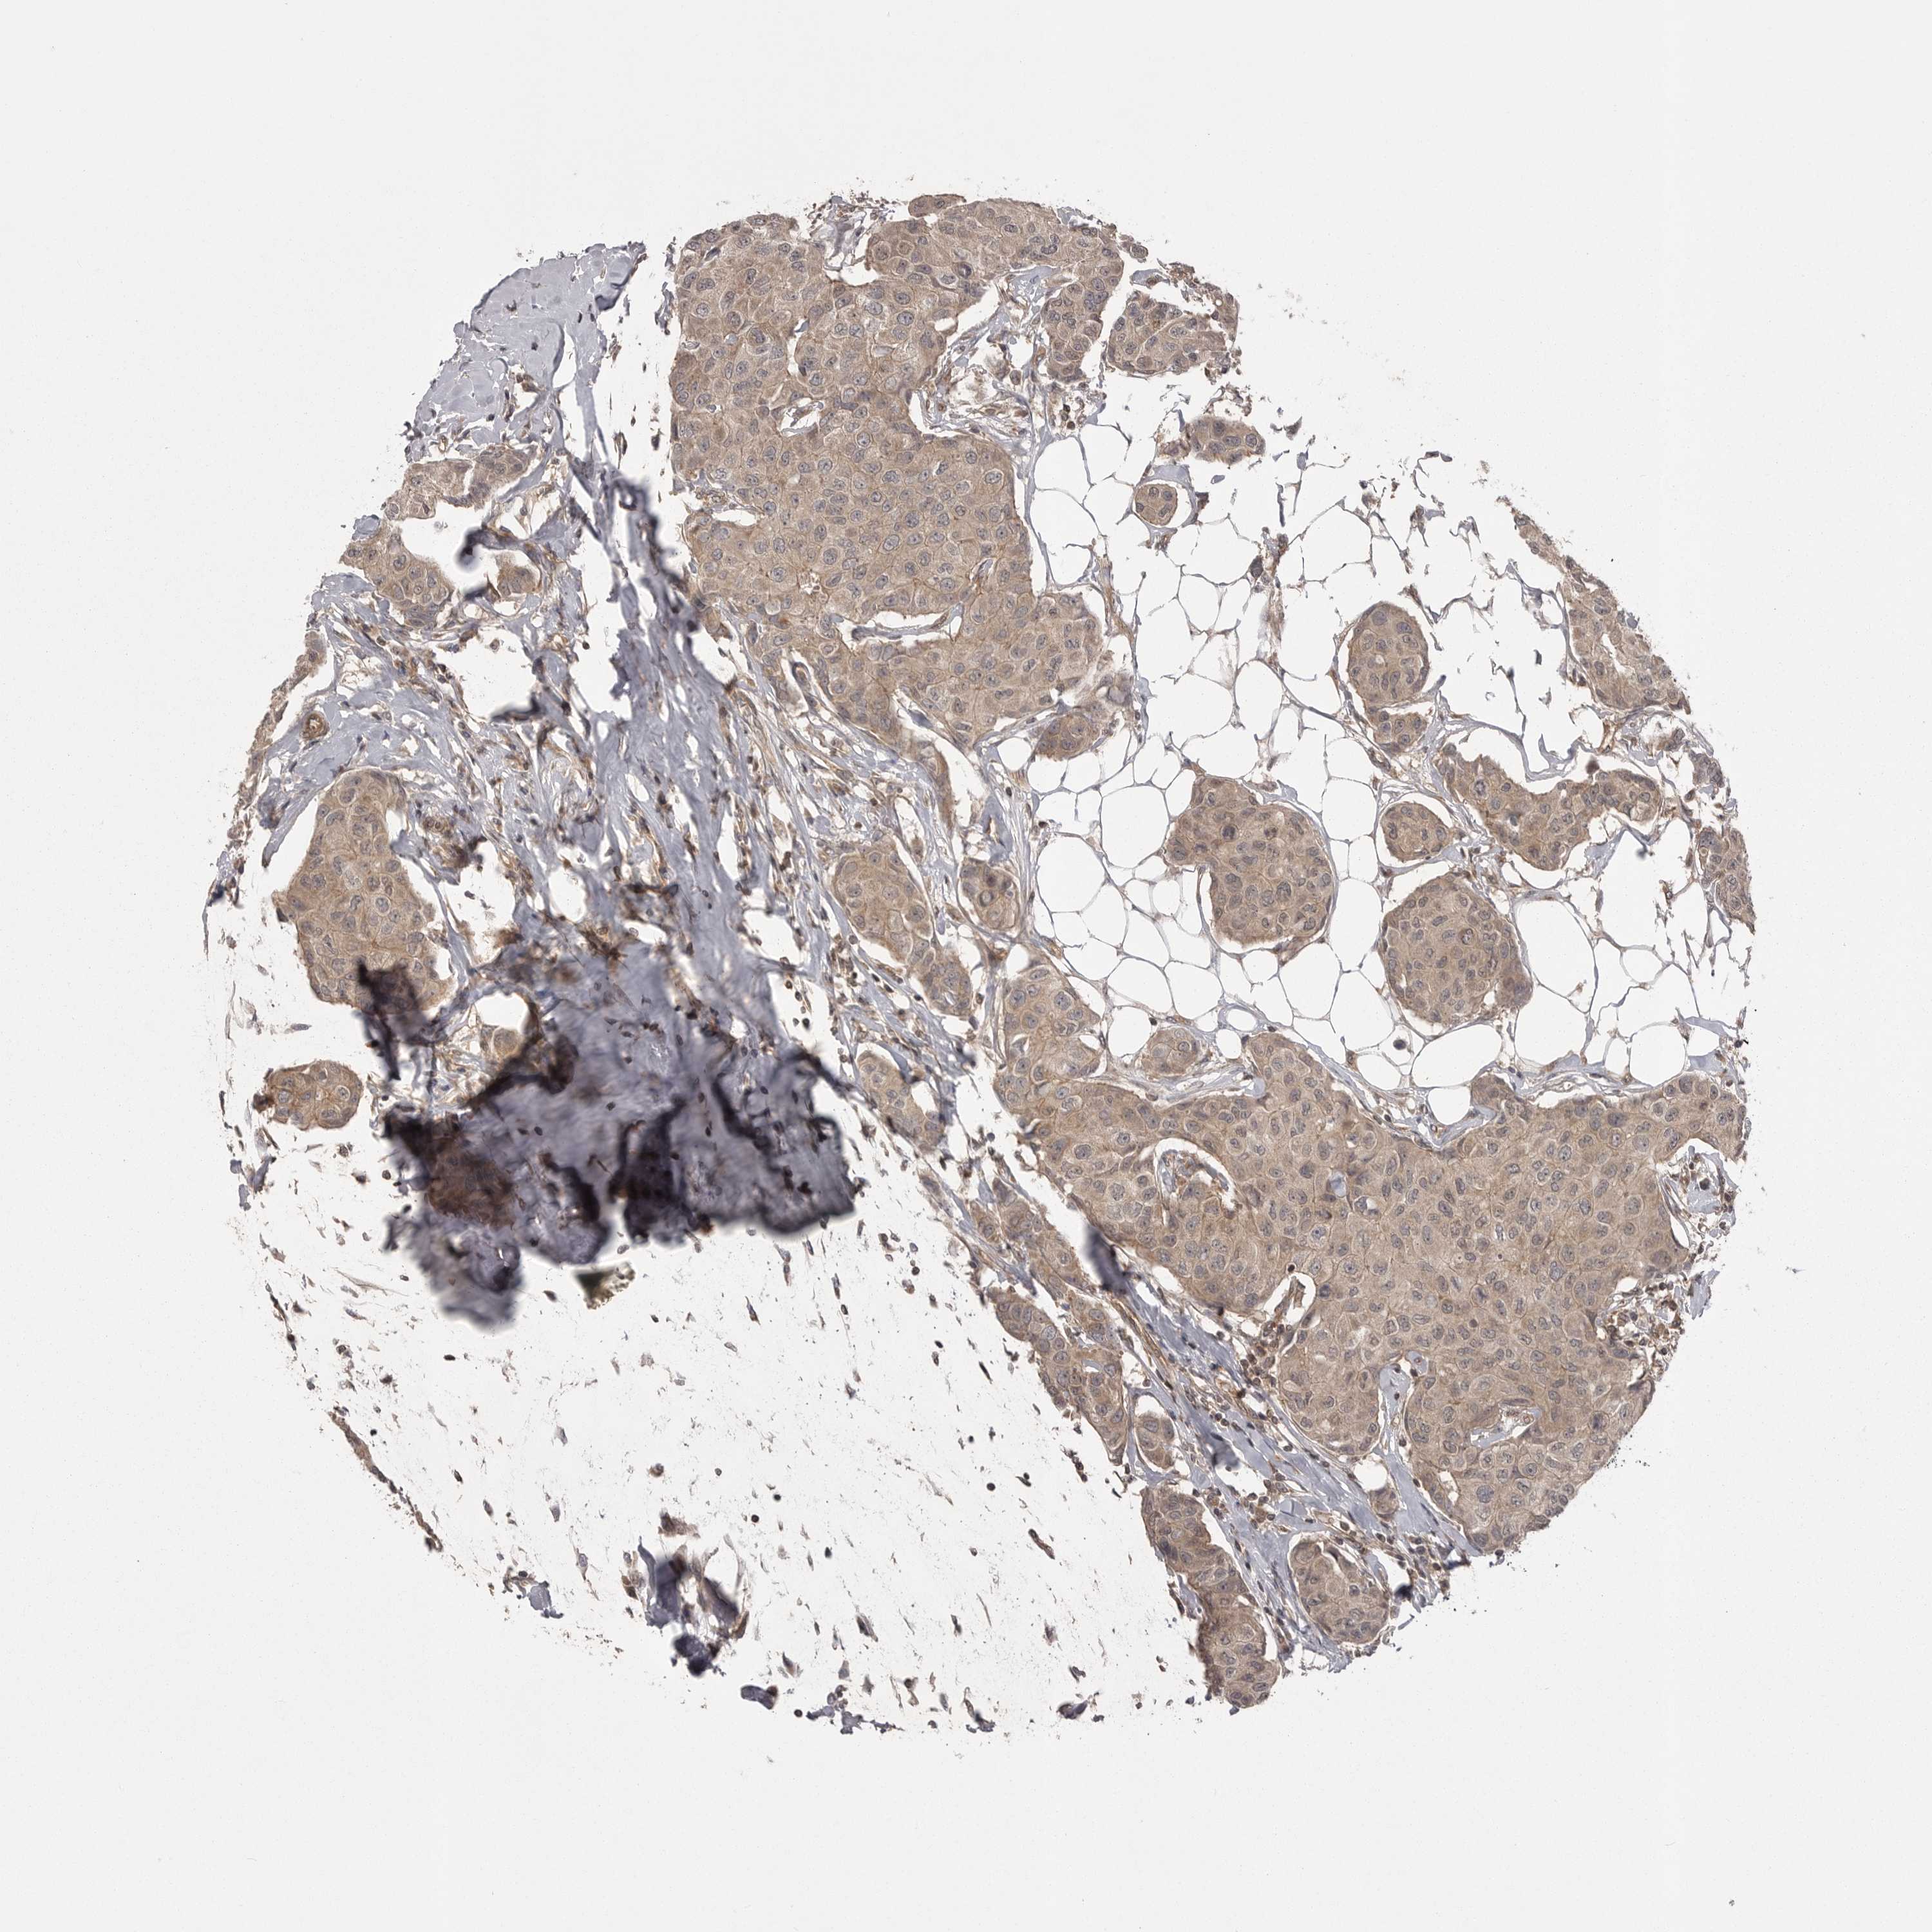

CANCER BREAST CANCER Show tissue menu

BRCA TCGA BRCA VALIDATION PROTEIN EXPRESSION